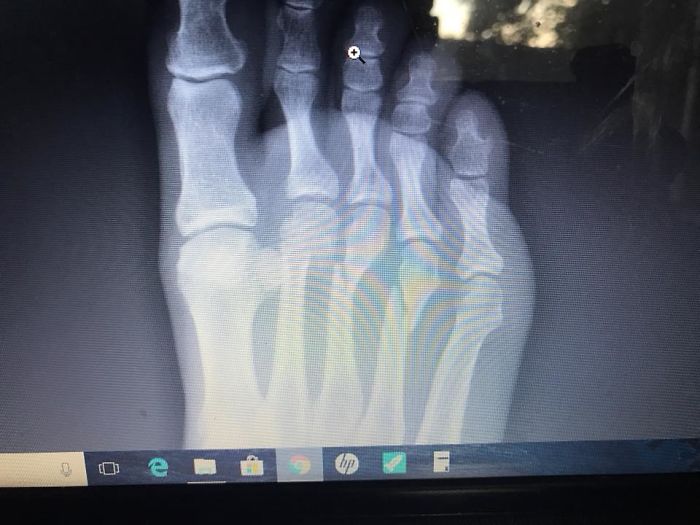

David hit the brakes so hard, he fractured the 2nd, 3rd, and 4th metatarsals of his right foot. Luckily, he won’t need surgery. He isn’t allowed to walk on his right foot for the next 6-8 weeks, though. But their son, William, probably had his guardian angel on duty.

Her husband, David, fractured the 2nd, 3rd, and 4th metatarsals of his right foot